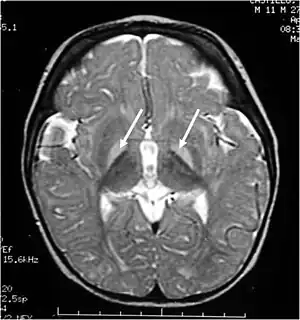

| Brain MRI showing hyperintense basal ganglia lesions on T2-weighted images. | |

These impairments are associated with lesions in the basal ganglia, auditory nuclei of the brain stem, and oculomotor nuclei of the brain stem. Cortex and white matter are subtly involved. Cerebellum may be involved. Severe cortical involvement is uncommon.